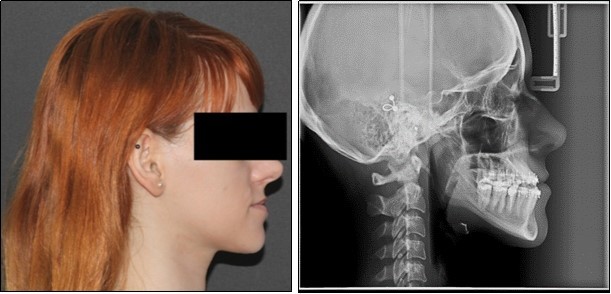

The pre-surgical orthodontic preparation successfully met the following objectives: levelling and aligning, flattening of curbe of Spee, proclination of the lower incisors and elimination of dental compensations. Before surgery, the patient had a normal position of the lower incisors, with IMPA 88 degrees. (Figure 4) Before surgery, a slight anterior open bite and an anterior crossbite could be observed, due to the elimination of dental compensations. Crimpable hooks were placed between each tooth on the 0.019x0.025 SS archwires, to allow placement of intermaxillary elastics after surgery. (Figure 5).

Figure 4.Pre-surgical extraoral photographs, after orthodontic preparation and preoperative lateral cephalometric radiograph

Pre-surgical extraoral photographs, after orthodontic preparation and preoperative lateral cephalometric radiograph